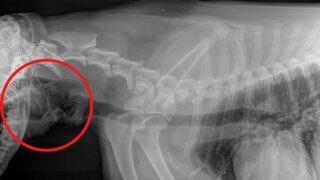

Hasta köpeğin röntgeninden çıkan sonuç herkesi şaşkına çevirdi! “Ölüyor zannettim”

13 yaşındaki Jip isimli bir köpek gece geç saatlerde nefes alma konusunda zorluk yaşamaya ve boğulma belirtileri göstermeye başlayınca sahibini korkuttu. Sahibi Jip’i veterinere götürdüğünde ise sağlık görevlileri köpeğin nefes borusuna sıkışan bir çift çorap fark etti.